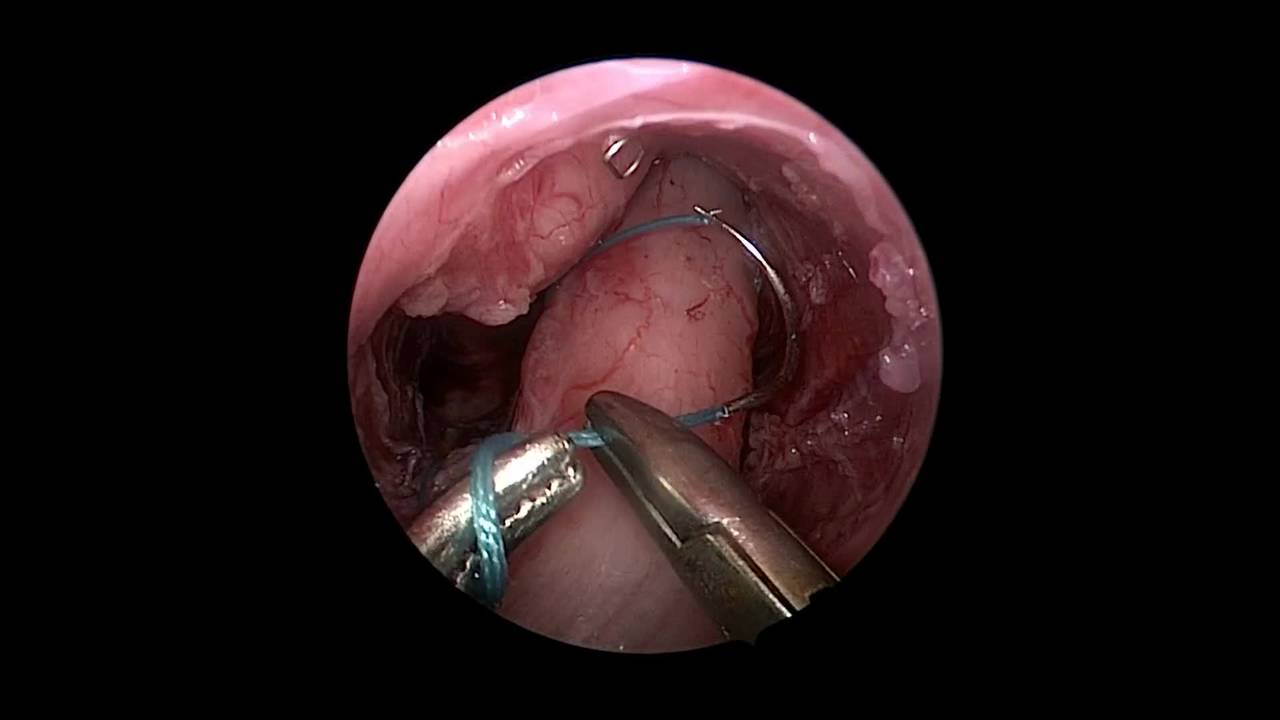

Laparoscopic Assisted Pull-through for Hirschsprung's Disease using a Just Right sealer by Dr. Steven Rothenberg.